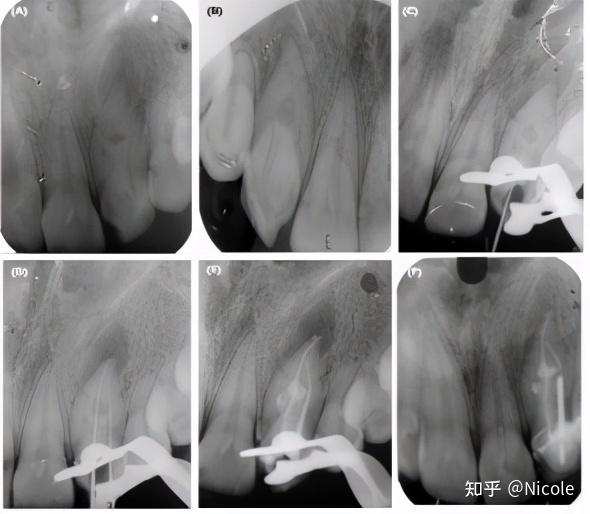

上颌侧切牙中的根管钙化与牙齿畸形

上颌侧切牙通常为一根管,平均根尖直径为0.